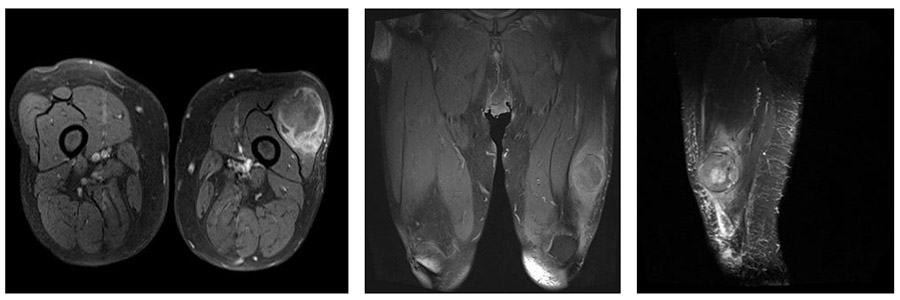

Ameliyat Öncesi: MR’da uyluk yerleşimli düzensiz sınırlı heterojen kitle görülmekte